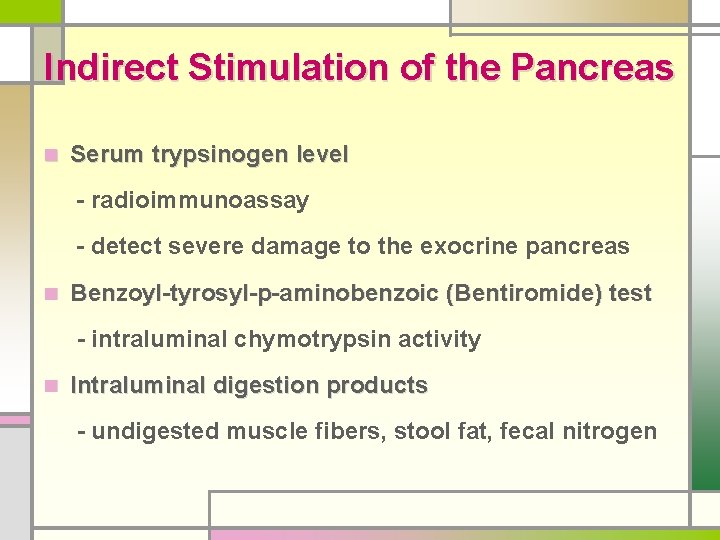

Indirect Stimulation of the Pancreas n Serum trypsinogen level - radioimmunoassay - detect severe damage to the exocrine pancreas n Benzoyl-tyrosyl-p-aminobenzoic (Bentiromide) test - intraluminal chymotrypsin activity n Intraluminal digestion products - undigested muscle fibers, stool fat, fecal nitrogen